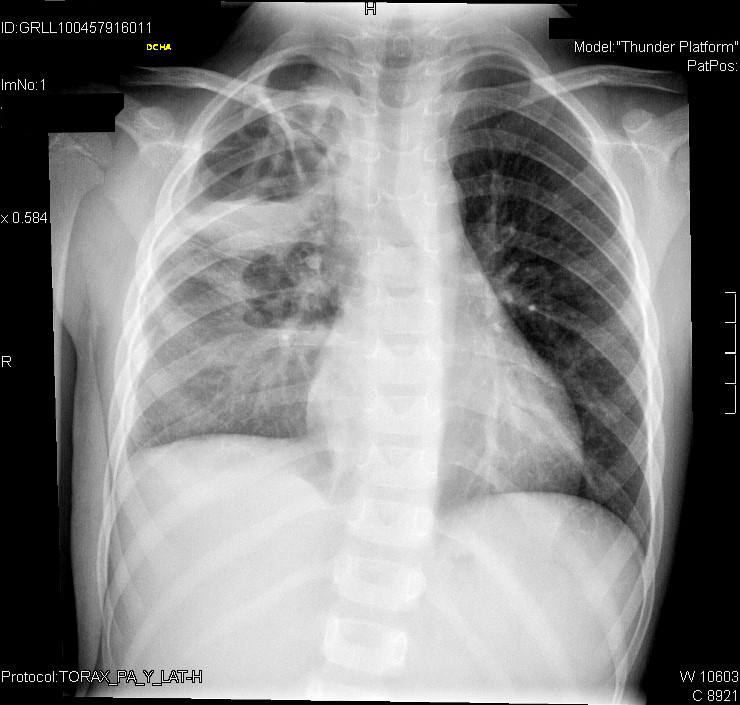

El quinto día de ingreso, que era el segundo con ampicilina a 300 mg/kg/día, nuestra paciente continúa con fiebre y excelente estado general. El drenaje del tubo pleural es escaso (< 35 ml) en las últimas 24 horas, por lo que lo retiramos. Los hemocultivos sacados al ingreso resultan negativos y la analítica en ese momento muestra 23,63 10E3/µl leucocitos y PCR de 343 mg/l.

Dos días después, el séptimo día de ingreso, continuaba con fiebre de hasta 39 °C, junto con tos y aumento de la rinorrea, por lo que pedimos un lavado nasal para gripe, que resultó negativo. La analítica, aunque sigue presentando datos de leucocitosis y PCR elevada, empieza a mejorar: 17,93 10E3/µl, PMN 85,4%, LM 8,7%, hemoglobina (Hb.) 9,1 g/dl, hematocrito (Hto.) 27,5%, plaquetas 650 10E3/µl, PCR 286,2 mg/l.

Le realizamos una radiografía de tórax de control.